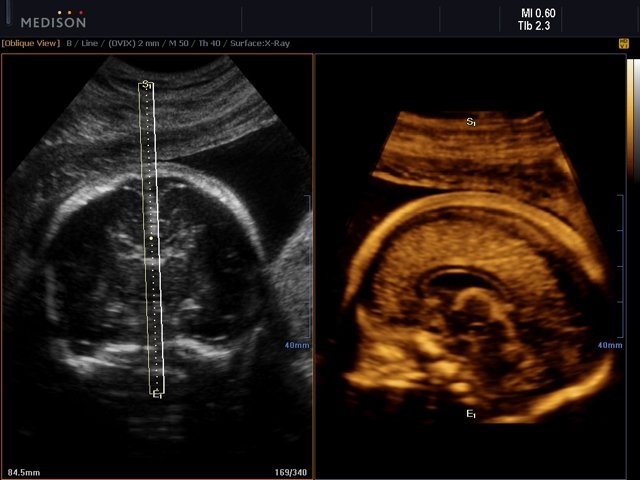

- OVIX (Oblique View eXtended) - получение фрагмента трехмерного изображения (в виде нескольких полупрозрачных сканов, последовательно наложенных один на другой) в направлении произвольного косого среза трехмерного объекта исследования.

- 3D - трехмерное сканирование объемными датчиками в статическом режиме в серой шкале и восстановление объемной структуры сосудов в режиме цветного / энергетического допплера (необходим Static 3D).

- 4D - трехмерное сканирование объемными датчиками в реальном масштабе времени (необходим Live 3D).

- Система Live 3D - трехмерное сканирование объемными датчиками в реальном масштабе времени (4D).